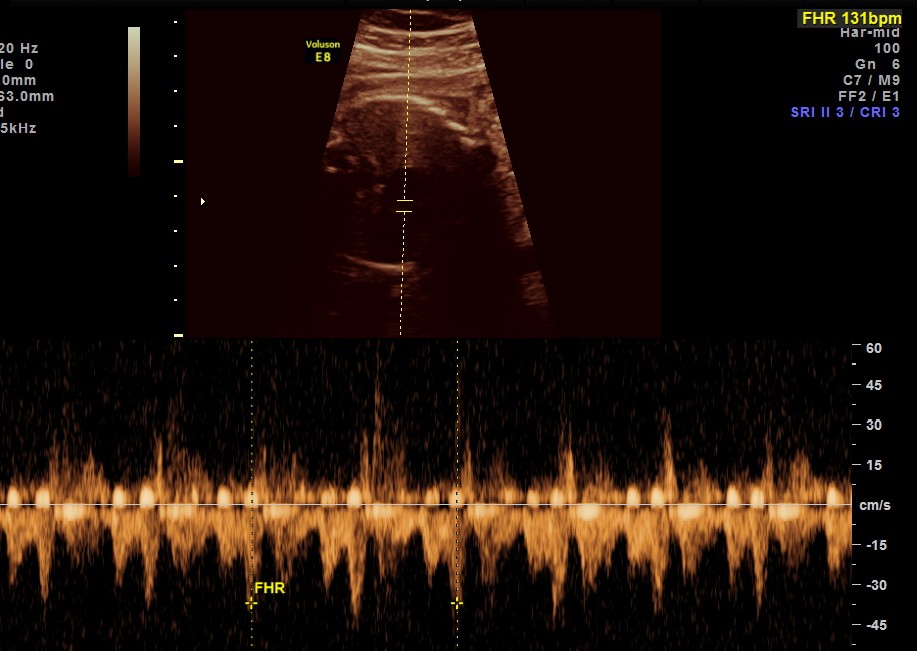

the following picture shows a normal conduction and rate

2. irregular rhythm of A.V.Dissociation, Bradycardia and normal rhythm